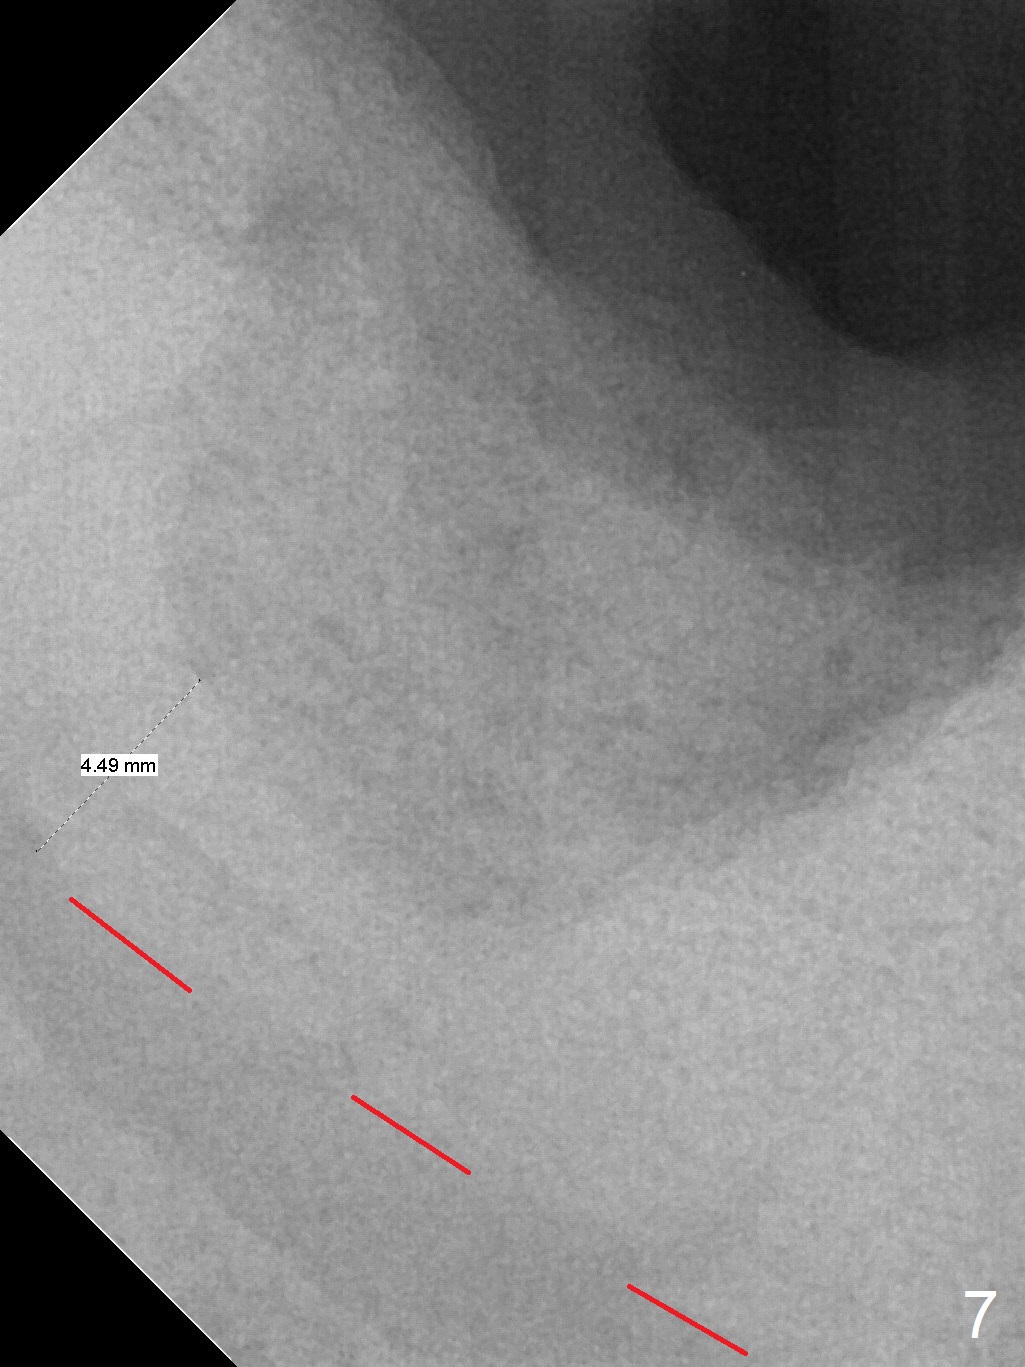

Extraction of the mobile tooth #31 (Fig.1) and debridement of the large socket are not difficult. But making osteotomy buccally does not seem to be easy. It will be difficult to restore. Instead, socket preservation is accomplished by filling the socket with approximately 1.5 cc of Mineralized Cortical/Cancellous allograft until the crest (Fig.2,5). The socket opening is closed by insertion of 4 pieces of PRF membranes (Fig.3) and 4-0 Chromic gut sutures (Fig.4). In the end of surgery, it appears that osteotomy in the center of the socket could be a better approach. Postop re-analysis of CT (Fig.6) and PA (Fig.7) shows that there is 3.9 mm of the native bone to support a 5.5x10 mm implant. Sinus Lift Master Kit should be used with 2 mm initial drill and 2.8 and 3.6 mm round drills with 4 mm stopper.

The socket heals 3 months postop (Fig.8,11). There is vertical loss of the ridge at #31 (Fig.9,10). The implant placed at #31 will be shorter than that at #30 (Fig.12). The patient will return for implant placement 4 months postop.